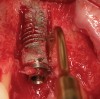

A 53-year-old woman presented with a failing implant in the No. 7 site (Figure 12 and Figure 13). Her desire was to eliminate infection and preserve esthetics. A team effort between the periodontist and restorative dentist to advocate for additional restorative dentistry as well as manage the patient’s expectation of time required was essential. In addition, the patient needed to have realistic expectations of a compromised outcome. Both the restorative dentist and the periodontist informed the patient about the difficulty of achieving this with acceptable esthetic results. Mutual emotional and technical support was required to successfully complete this case, from initial grafting of the defect to placement of anterior restorations (Figure 14 through Figure 23).